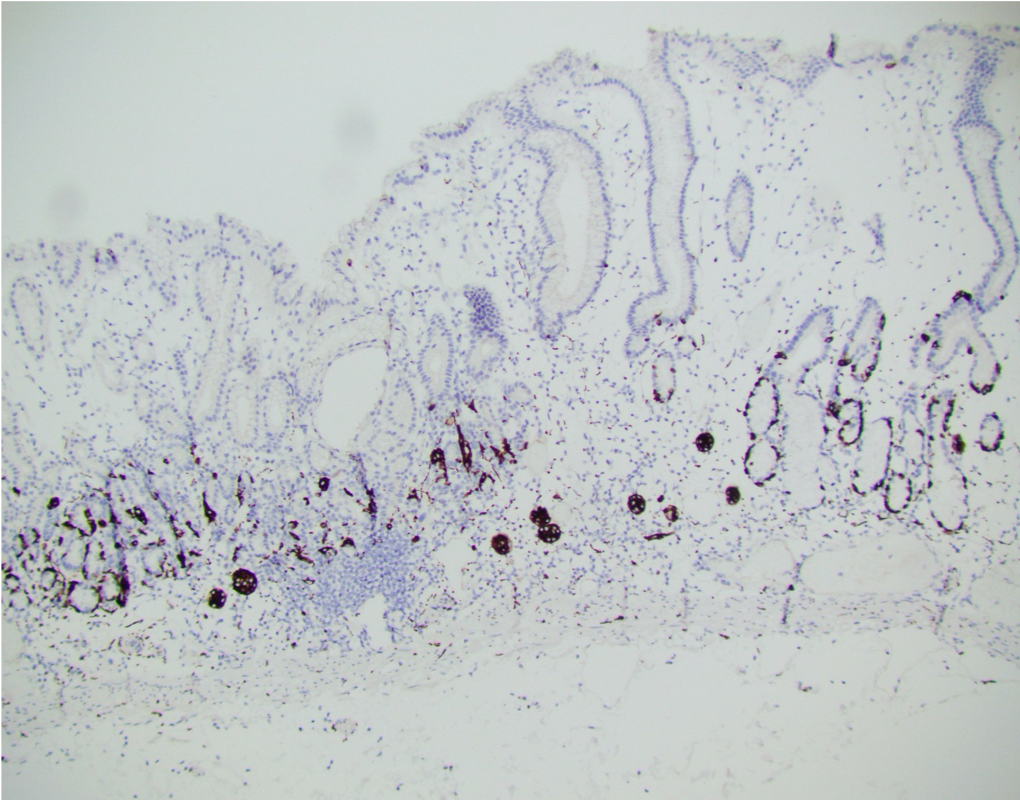

A 56-year-old female underwent upper endoscopy for dyspepsia. A 1 cm gastric nodule was found and biopsied. The histological findings are shown in Figure1 (low power) and Figure 2 (high power). Synaptophysin immunostaining of the tumor (Figure 3) and the background mucosa (Figure 4) are included.

This NET is occurring in a background of atrophic oxyntic mucosa, also known as autoimmune metaplastic atrophic gastritis ( AMAG), which typically shows nodular neuroendocrine cell hyperplasia (ECL) highlighted by synaptophysin stain ( Figure 4}. Intestinal metaplasia is also seen in Figure 1. Psedopyloric metaplasia (another characteristic) feature cannot be appreciated in the provided photographs. Even though Gastrin stain is not provided, the staining pattern of neuroendocrine cells is not that of G cells. Type 1 gastric NETs are typically small, multiple, low grade, associated with antibodies for intrinsic factor/ parietal cell, often have iron deficiency or B12 deficiency, and are managed by endoscopic surveillance. Type 3 NETs are sporadic, not associated with atrophic corpus gastritis. Type 2 are rare, can show ECL hyperplasia, but are associated with MEN1/gastrinoma and parietal cell hyperplasia.